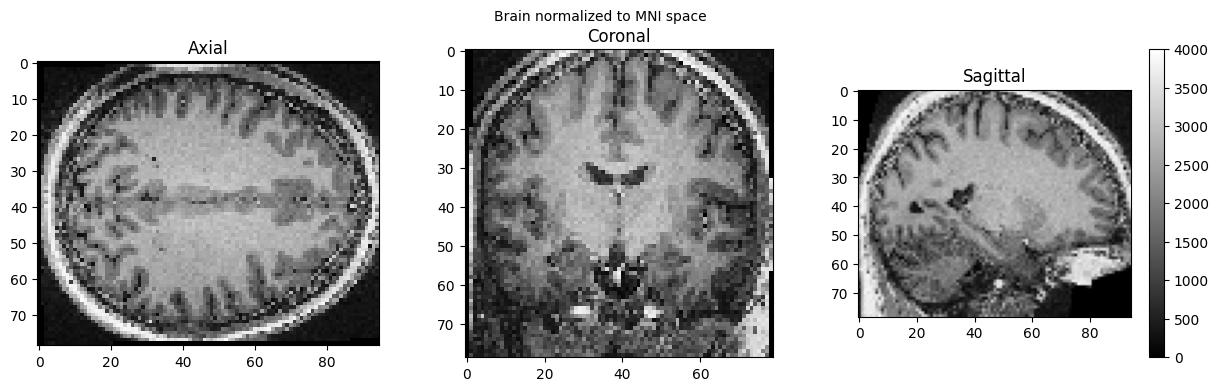

import nipype.interfaces.spm as spm

norm12 = spm.Normalize12()

norm12.inputs.image_to_align = './sub-01_ses-01_7T_T1w_defaced.nii'

norm12.run()

brain_full = nib.load('./wsub-01_ses-01_7T_T1w_defaced.nii').get_fdata()

view_slices_3d(brain_full, slice_nbr=50, vmin=0, vmax=4000, title='Brain normalized to MNI space')